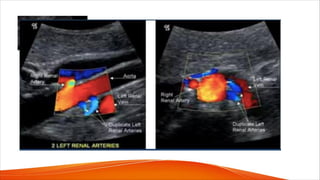

Duplicate artery problems

• In hypertensive patients, the documentation or exclusion of a renovascular

etiology requires the assessment of the main renal artery, whether single or

duplicate, and the segmental arteries in the renal hilum.

• Although it is accepted that the smaller accessory and polar arteries do not

increase the risk of hypertension, the terms duplicated, accessory, and polar

are often used interchangeably

• It is therefore important to understand renal arterial terminology and not to

erroneously denote arteries as duplicate, accessory, or polar, as the clinical

significance and management of these vessels is different.

• Duplicated main renal arteries are usually similar in size and supply

similar proportions of the renal parenchyma.

• Accessory and polar arteries are aberrant arterial branches that usually

supply a smaller portion of the kidney

• Branches to the upper or lower renal poles may be described as polar

arteries.

• Detection rate for supernumerary arteries using duplex ultrasound

(including color flow imaging) seems to be quite poor.

• Accessory renal arteries rarely cause hypertension or significant ischemia;

therefore one could argue that their visualization is unimportant.

• Duplicated main renal arteries, however, can be repaired, and their

detection is clinically significant. One maybe normal and another

stenosed, leading to ischemic changes. Therefore all duplicate arteries

should be assessed.